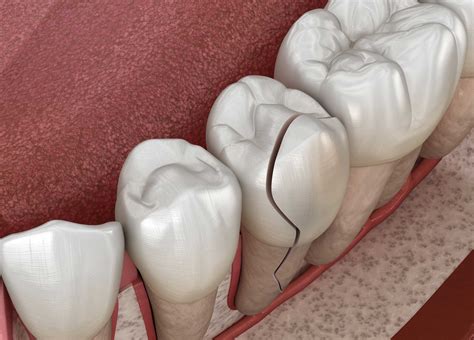

Split Tooth The tooth is split into two distinct segments. Extraction or complex root therapy.

Vertical Root Fracture Begins in the root and moves upward. Extraction is often required.

💡 Note: If you experience persistent throbbing pain or notice localized swelling near the gum line, seek dental attention immediately, as these are often indicators of an infection resulting from a deep crack.